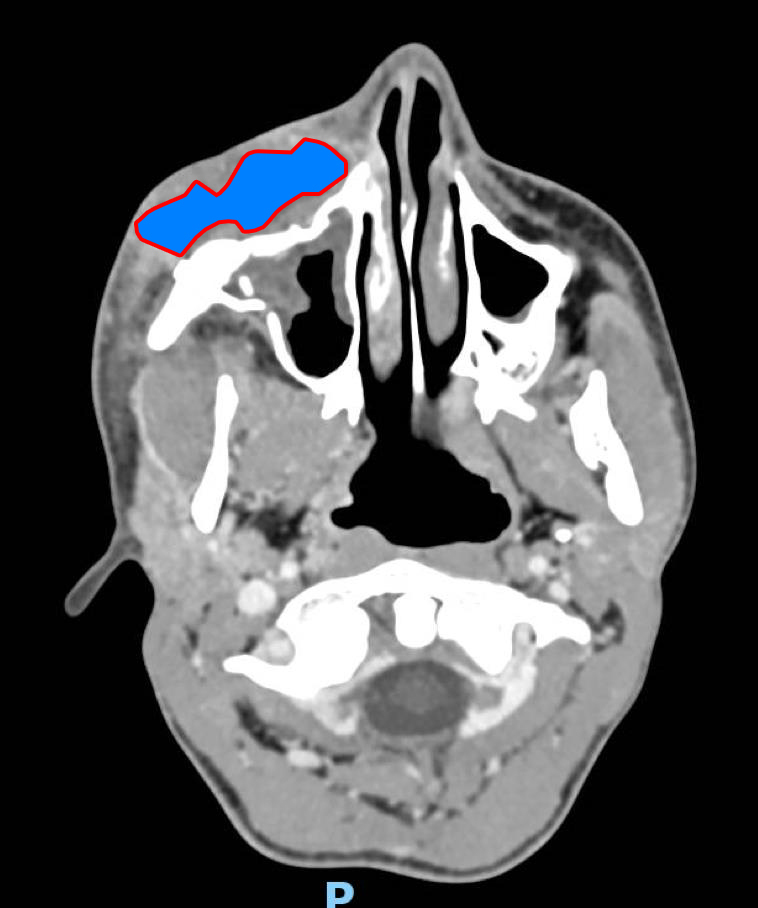

De garde, vous êtes appelé en salle de surveillance post-interventionnelle (SSPI) dans votre hôpital où vient d'être admis un patient conduit sur place par le service d'aide médicale d'urgence (Samu). Il s’agit d’un jeune homme de 20 ans, Monsieur D. Il aurait été victime, entre autres, d’un tir de Flash-Ball lors d’une rixe. Le projectile l’a atteint au niveau de la pommette et de l’orbite droites. Il présente une plaie de la région jugale haute, un œdème des paupières supérieure et inférieure. Vous ne visualisez pas le globe oculaire spontanément. Il est hémodynamiquement stable.

Traumatisme orbitaire = à risque de fracture des parois de l’orbite et donc d’incarcération d’un muscle oculomoteur.